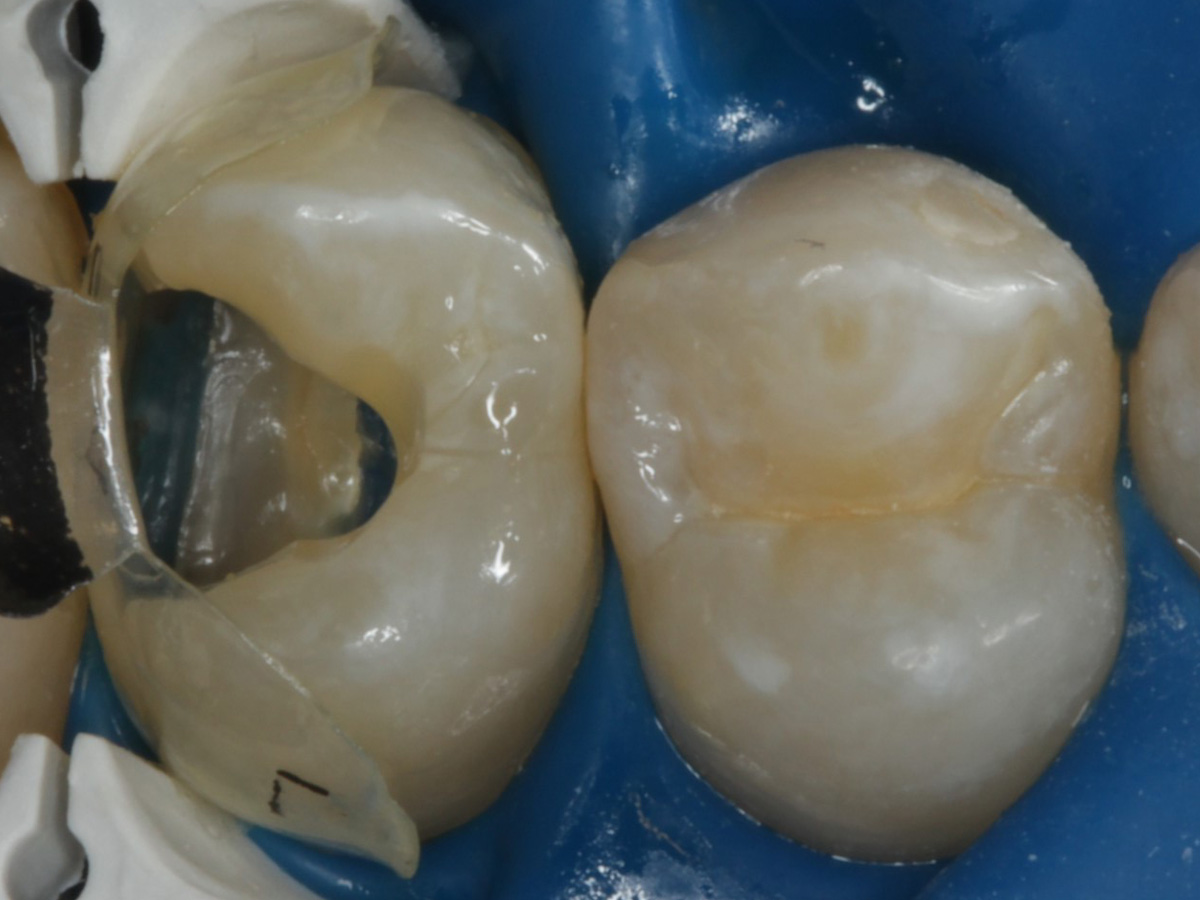

Folgesitzung: Trepanation Zahn 25

Wurzelkanäle gefüllt

Kontrollröntgenaufnahme

Kompositrestauration nach „Schachtverschluß“; keine Krone geplant